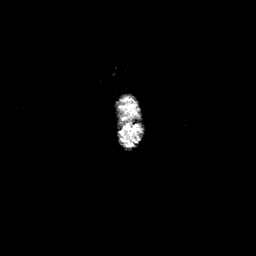

Glioma overlay -- Slice #118

[Home][Help][Clinical] Slice 118